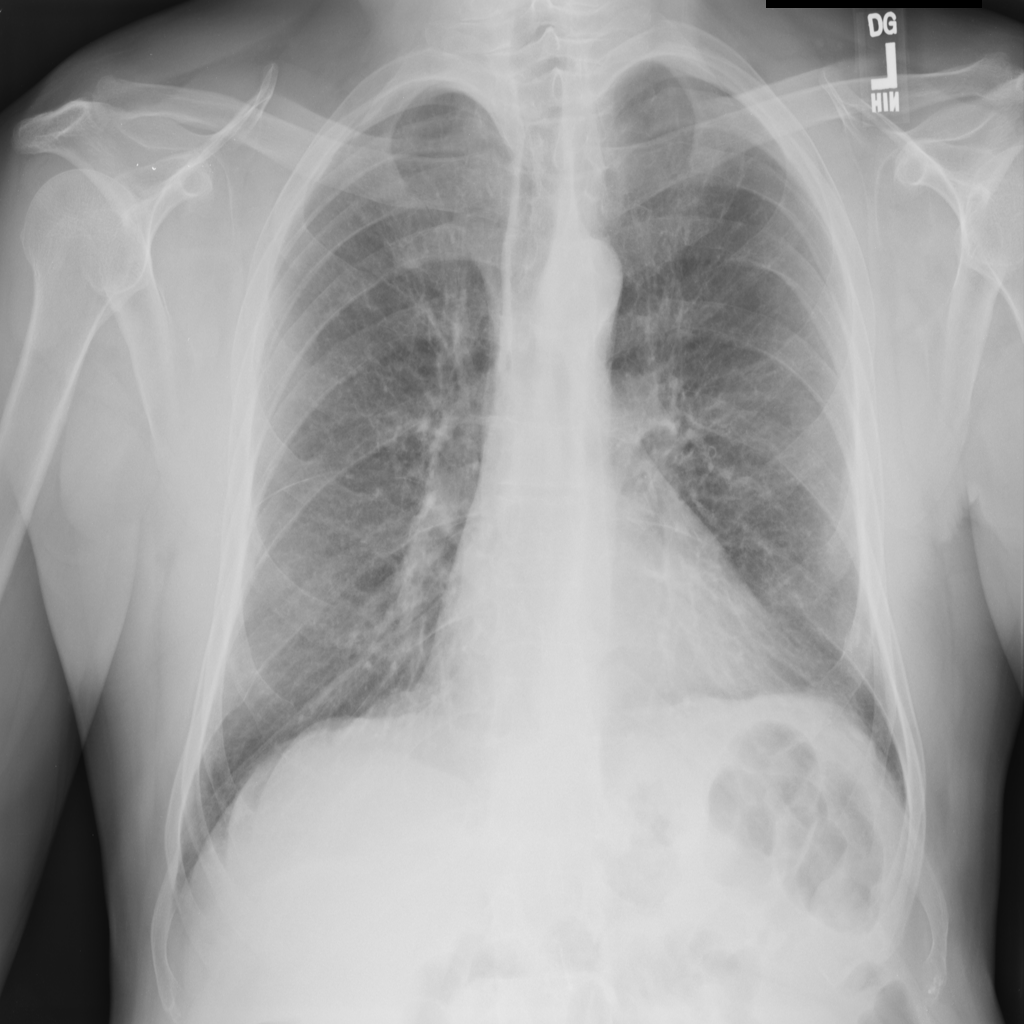

PAT-894B · IMG-000Emphysema

PAT-894B · IMG-000

PA